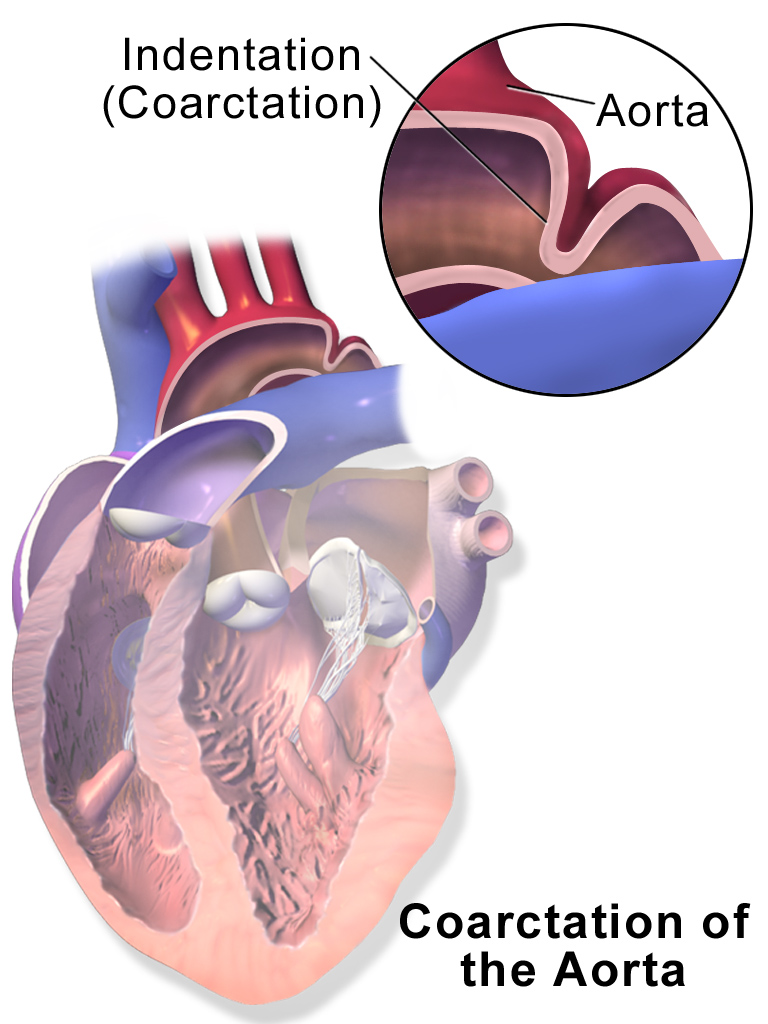

Coarctation of the Aorta

Coarctation of the aorta results in an abnormal narrowed portion of the aorta.

Coarctation of the aorta is separated into juvenile and adult versions.

Juvenile version of coarctation of the aorta

A patent ductus arteriosus (PDA), infantile form is connected.

Coarctation is located distal (after) to the aortic arch and proximally (before) to the patent ductus arteriosus (PDA).

Coarctation of the aorta presents in babies as lower extremity cyanosis, mostly after birth.

Coarctation of the aorta is linked to Turner syndrome (monosomy X).

Adult version of coarctation of the aorta

A patent ductus arteriosus (PDA) is not connected to adult form of coartctation of the aorta.

After (distal to) the aortic arch is where the coarctation is typically located in adults.

Coarctation of the aorta in adults typically presents with:

- Hypertension in the upper extremities

- Hypotension with weak pulses in the lower limbs

Radiology of coarctation of the aorta classically shows “notched ribs” on an x-ray due to collateral vessels.

Coarctation of the aorta is linked with the bicuspid aortic valve.